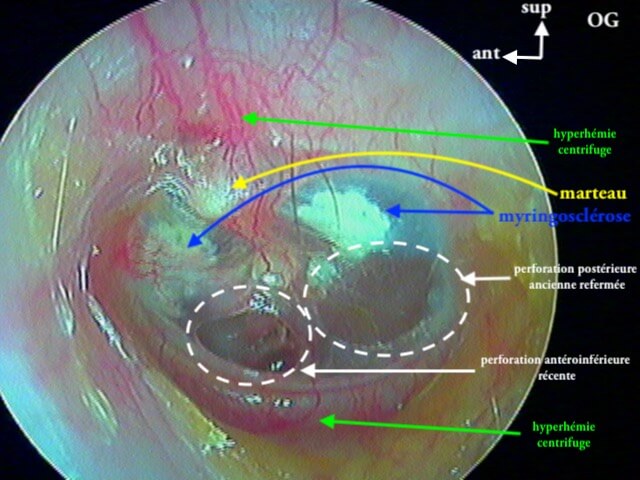

3/2 barotraumatique

– stade I : hyperhémie du manche du marteau et de la pars flaccida ;

– stade II : tympan rétracté, congestif, immobile

– stade III : aspect d'otite séromuqueuse

– stade IV : aspect otite séro-hémorragique, otohématome

– stade V : perforation

Ici des stades V perforés

Ici une otite séromuqueuse gauche perforée cicatrisée à 1 mois (cicatrice inférieure)

7 MYRINGOSCLÉROSE (ou TYMPANOSCLÉROSE)

Surcharge calcaire de la couche conjonctive tympanique: AUCUNE conséquence anatomique ou fonctionnelle (auditive), gêne parfois en cas de tympanoplastie. On parle plus de tympanosclérose quand ces plaques de calcaires (issues d'infections antérieures cicatrisées) sont dans la caisse; et de myringosclérose quand elles ne touchent que le tympan. En les voyant cela vous permettra d'affirmer que le patient·e a eu des otites dans l'enfance et puis c'est tout! Ces plaques sont superficielles et le tympan est normal, à ne pas confondre avec un cholestéatome.